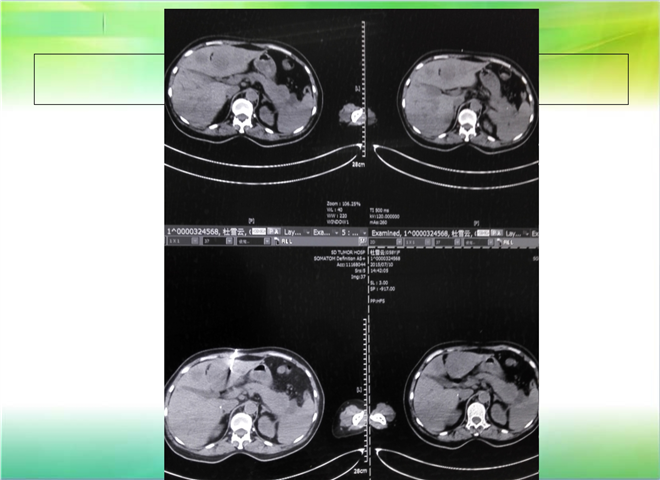

CT引导下穿刺活检术